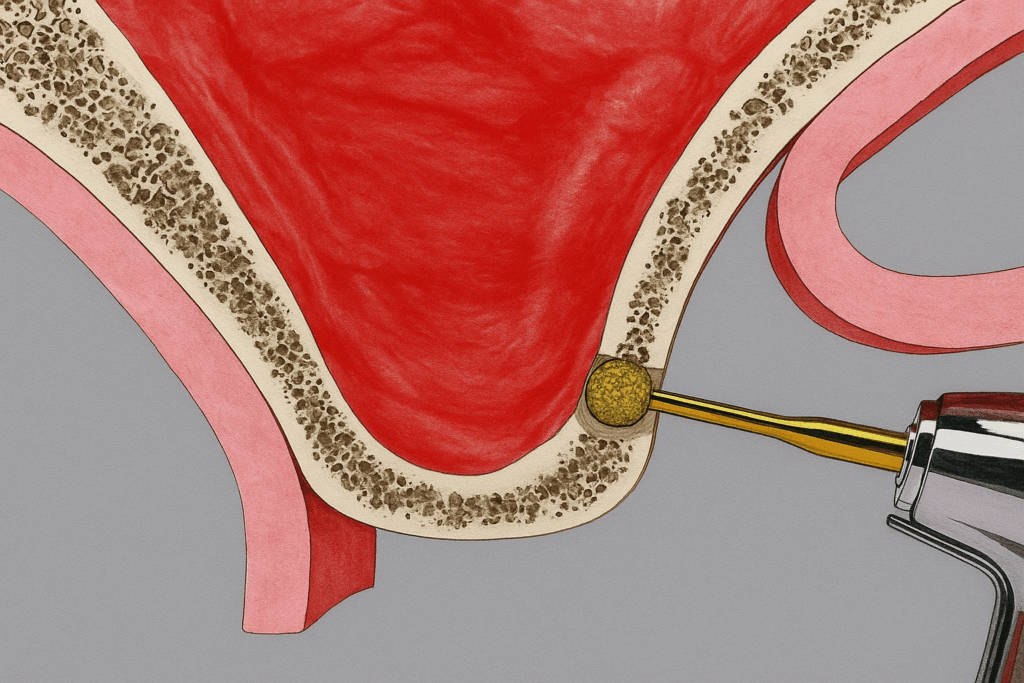

그 방법으로는 상악동 거상술이라 하여

얇아진 치조골의 상부를 들어 올린 후

그 공간에 이식재를 보강하는 방식으로

임플란트가 자리 잡을 수 있는

공간을 확보하는 것입니다.

이 방식은 치조정 접근법과

측방 접근법으로 나뉘게 되는데,

지금처럼 치조골이 흡수가 심한 경우

측방 접근법을 시행합니다.

치조골의 옆쪽,

즉 측면에 작은 창을 내고

그 부위 상악동막을 들어 올립니다.

그리고 생긴 공간에 이식재를 채워

안정적인 식립 환경을 갖추기 위해

회복 기간을 갖게 됩니다.

측면에서 진행되는 과정이다 보니

많은 양의 뼈 재료를 채워 넣기 적합하지만,

절개 부위가 다소 큰 편에 속하고

술자의 따라 예후가 달라지기 때문에

고난이도의 시술이라 할 수 있습니다.